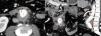

La angiografía computarizada multifásica (angio-TC) es de elección en situaciones de urgencia, permitiendo una evaluación detallada de las estructuras vasculares. La resonancia magnética, la ecografía y las técnicas de medicina nuclear pueden ser útiles en ciertos casos.

Los signos directos en angio-TC incluyen la visualización del tracto fistuloso y la extravasación de contraste, no obstante, es más frecuente identificar signos indirectos como anormalidades de la pared aórtica, engrosamiento de la grasa perivascular o colecciones. Además, hay ciertas condiciones que pueden imitar a las fístulas, lo que hace esencial un diagnóstico diferencial.

Multiphasic computed tomography angiography (CTA) is the gold standard in emergency situations, enabling a detailed evaluation of vascular structures. Magnetic resonance imaging, ultrasound and nuclear medicine techniques may be useful in certain cases.

Direct signs in CTA include visualisation of the fistulous tract and contrast extravasation. However, it is more common to identify indirect signs such as aortic wall abnormalities, perivascular fat thickening or collections. In addition, other conditions can mimic fistulae, making a differential diagnosis essential.